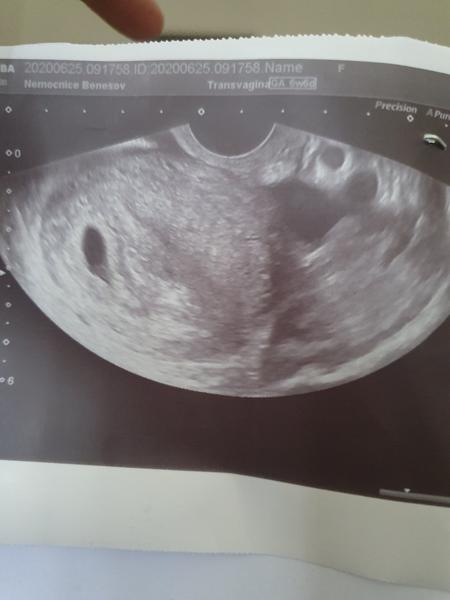

První ultrazvuk. Co na to říkáte?

V kolikatem týdnu vám ultrazvuk dělali? 😊

@verunkaded je to na fotce..

Gratulace. ❤️Příště muže být srdíčko a nemusí. 🙂 Já ho měla až celkem pozdě v 8+2 🙂)

@himanka že si těhotná, gratuluji. Další ultrazvuk už půjde vidět i srdíčko.